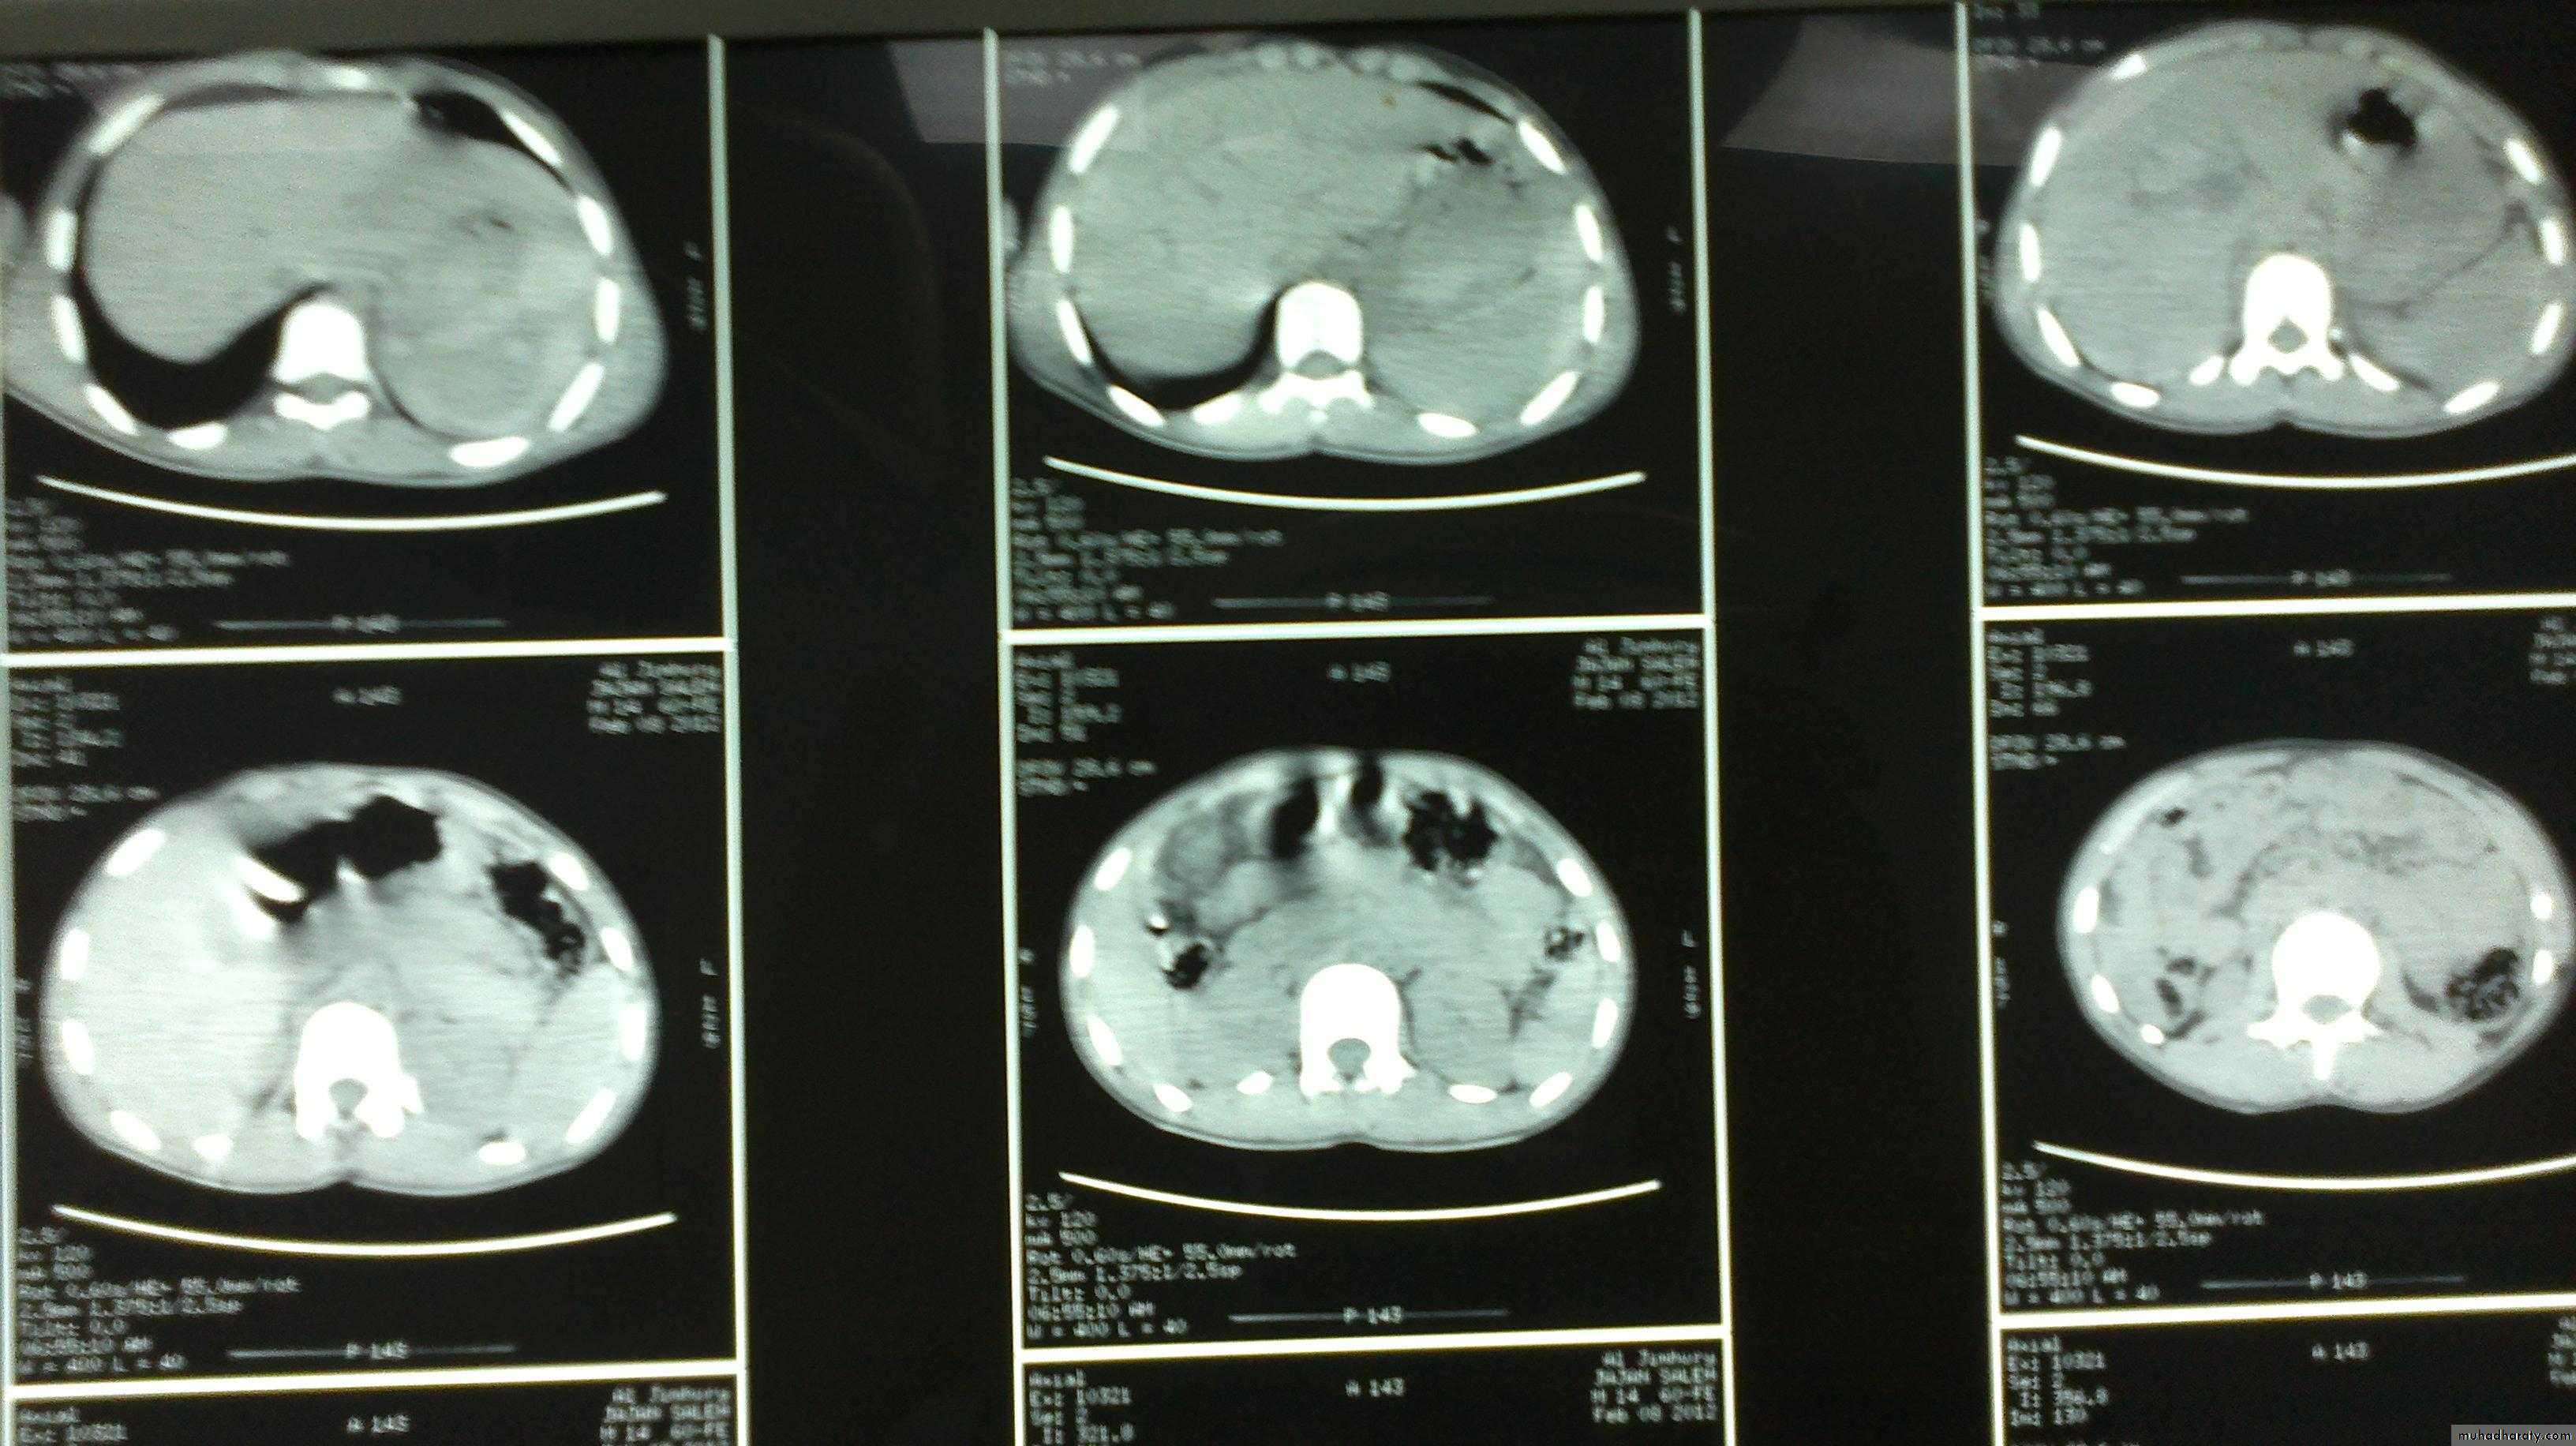

Ultrasonography; Determine the size & consistency SOL, cystic or solid CT scan; Better in determing the nature of suspected splenic pathology. MRI scan similar value to CT scan

Clinical signs of ruptured spleen: General signs of internal hge Left upper quadrants guarding and tenderness.Kehr’s sign Shifting dullness Fullnes in the pelvis Diagnosis: Abdominal ultrasonography (FAST) CT scan

CT scan *isolated injury.

Complications: Rupture: Subphrenic abscess Peritonitis Diagnosis: Ultrasound CT scan Treatment: Underlying cause drainage